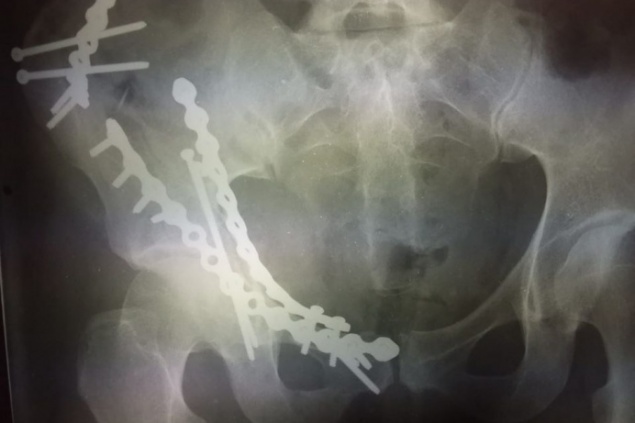

— Была проведена большая операция, 10 фрагментов левой части таза скрупулезно нам пришлось сопоставлять в течение 3 часов... Опасность этой травмы в том, что была раздроблена большая губчатая кость, которая обильно кровит. Кровопотеря у пациентки составила 1,5 литра во время травмы и 1,5 литра во время операции. Пациентка сейчас продолжает лечение, — рассказывает заведующий отделением Константин Тутытнин.